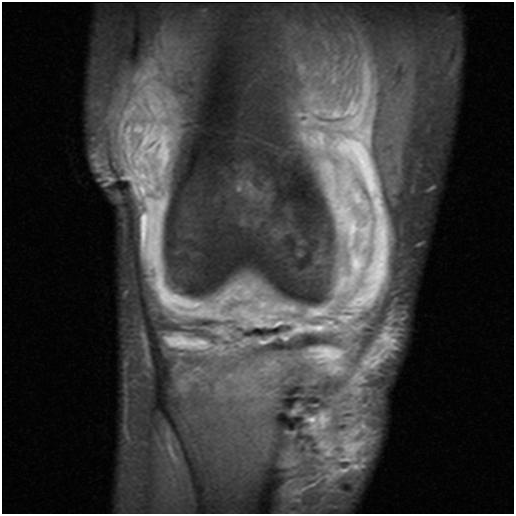

A 24-year-old white male sustained a right medial meniscal tear and anterior cruciate ligament (ACL) injury in January 2006. He was wrestling with some friends over a hard surface (concrete), when he sustained a twisting type injury to his right knee and felt a pop. He underwent a right arthroscopy for ACL reconstruction with a bone-tendon-bone cadaveric ACL allograft on September 16th, 2006. We could not determine information on antibiotic prophylaxis. His rehabilitation was unremarkable until January 2007, when he developed pain in his right knee, a new pop on his knee, with progressive swelling and joint effusion. He received a trial of physical therapy and nonsteroidal anti-inflammatory drugs (NSAIDs), with no resolution. He was evaluated by his orthopedic surgeon, who performed an arthrocentesis, relieving the swelling and pain. The fluid was not cultured. However, the swelling and the pain came back. Two more arthrocentesis were performed on February 5th and 15th. Both cultures from synovial fluid recovered Candida glabrata, which was believed to be responsible for his effusion and knee pain (cell count and differential were not available). He was started on IV caspofungin (loading dose: 70mg, maintenance: 50mg IV every day), with persistent swelling, pain with constant range of motion, and instability in his knee. He denied any numbness or tingling of the leg. He denied any other aches, bumps, and bruises. He also denied any current fever, chills or night sweats. His past medical history is unremarkable. He was not taking any medication in addition to caspofungin. He did not have any allergic reactions. He worked as a welder. He smokes two to three cigarettes per day, and denied alcohol or intravenous drug use (IVDU). His physical examination revealed a well-developed white male in no acute distress. His right lower extremity revealed a moderate effusion of the right knee, with considerable soft tissue swelling and mildly warmer than the left knee. Range of motion was from full extension to approximately 115 degrees flexion. The knee has a positive Lachman sign, the McMurray test was difficult to assess, and muscle strength was normal. He had a brisk capillary refill, and conserved sensation to light touch throughout his extremities. Surgical incisions from previous arthrocentesis did not show evidence of infection. Except for mild thrombocytosis (platelet count: 430x106/mL), complete blood count and basic chemistry were within normal limits. Erythrocyte sedimentation rate was 35mm, and C-reactive protein was 2.5mg/dL. An MRI showed a chronically ruptured ACL graft, with resorption of the graft, proximal retention screws extending into the joint space, and joint effusion (Figures 1-3). X-ray imaging showed osteolysis at the level of the tibial tunnel. An Infectious Diseases consultation was obtained, after concern for C.glabrata septic arthritis and possible osteomyelitis. Caspofungin was continued, and a new arthrocentesis was performed (cell count or differential were not performed).

Figure 1 Large effusion with multiple loose bodies on suprapatellar pouch.